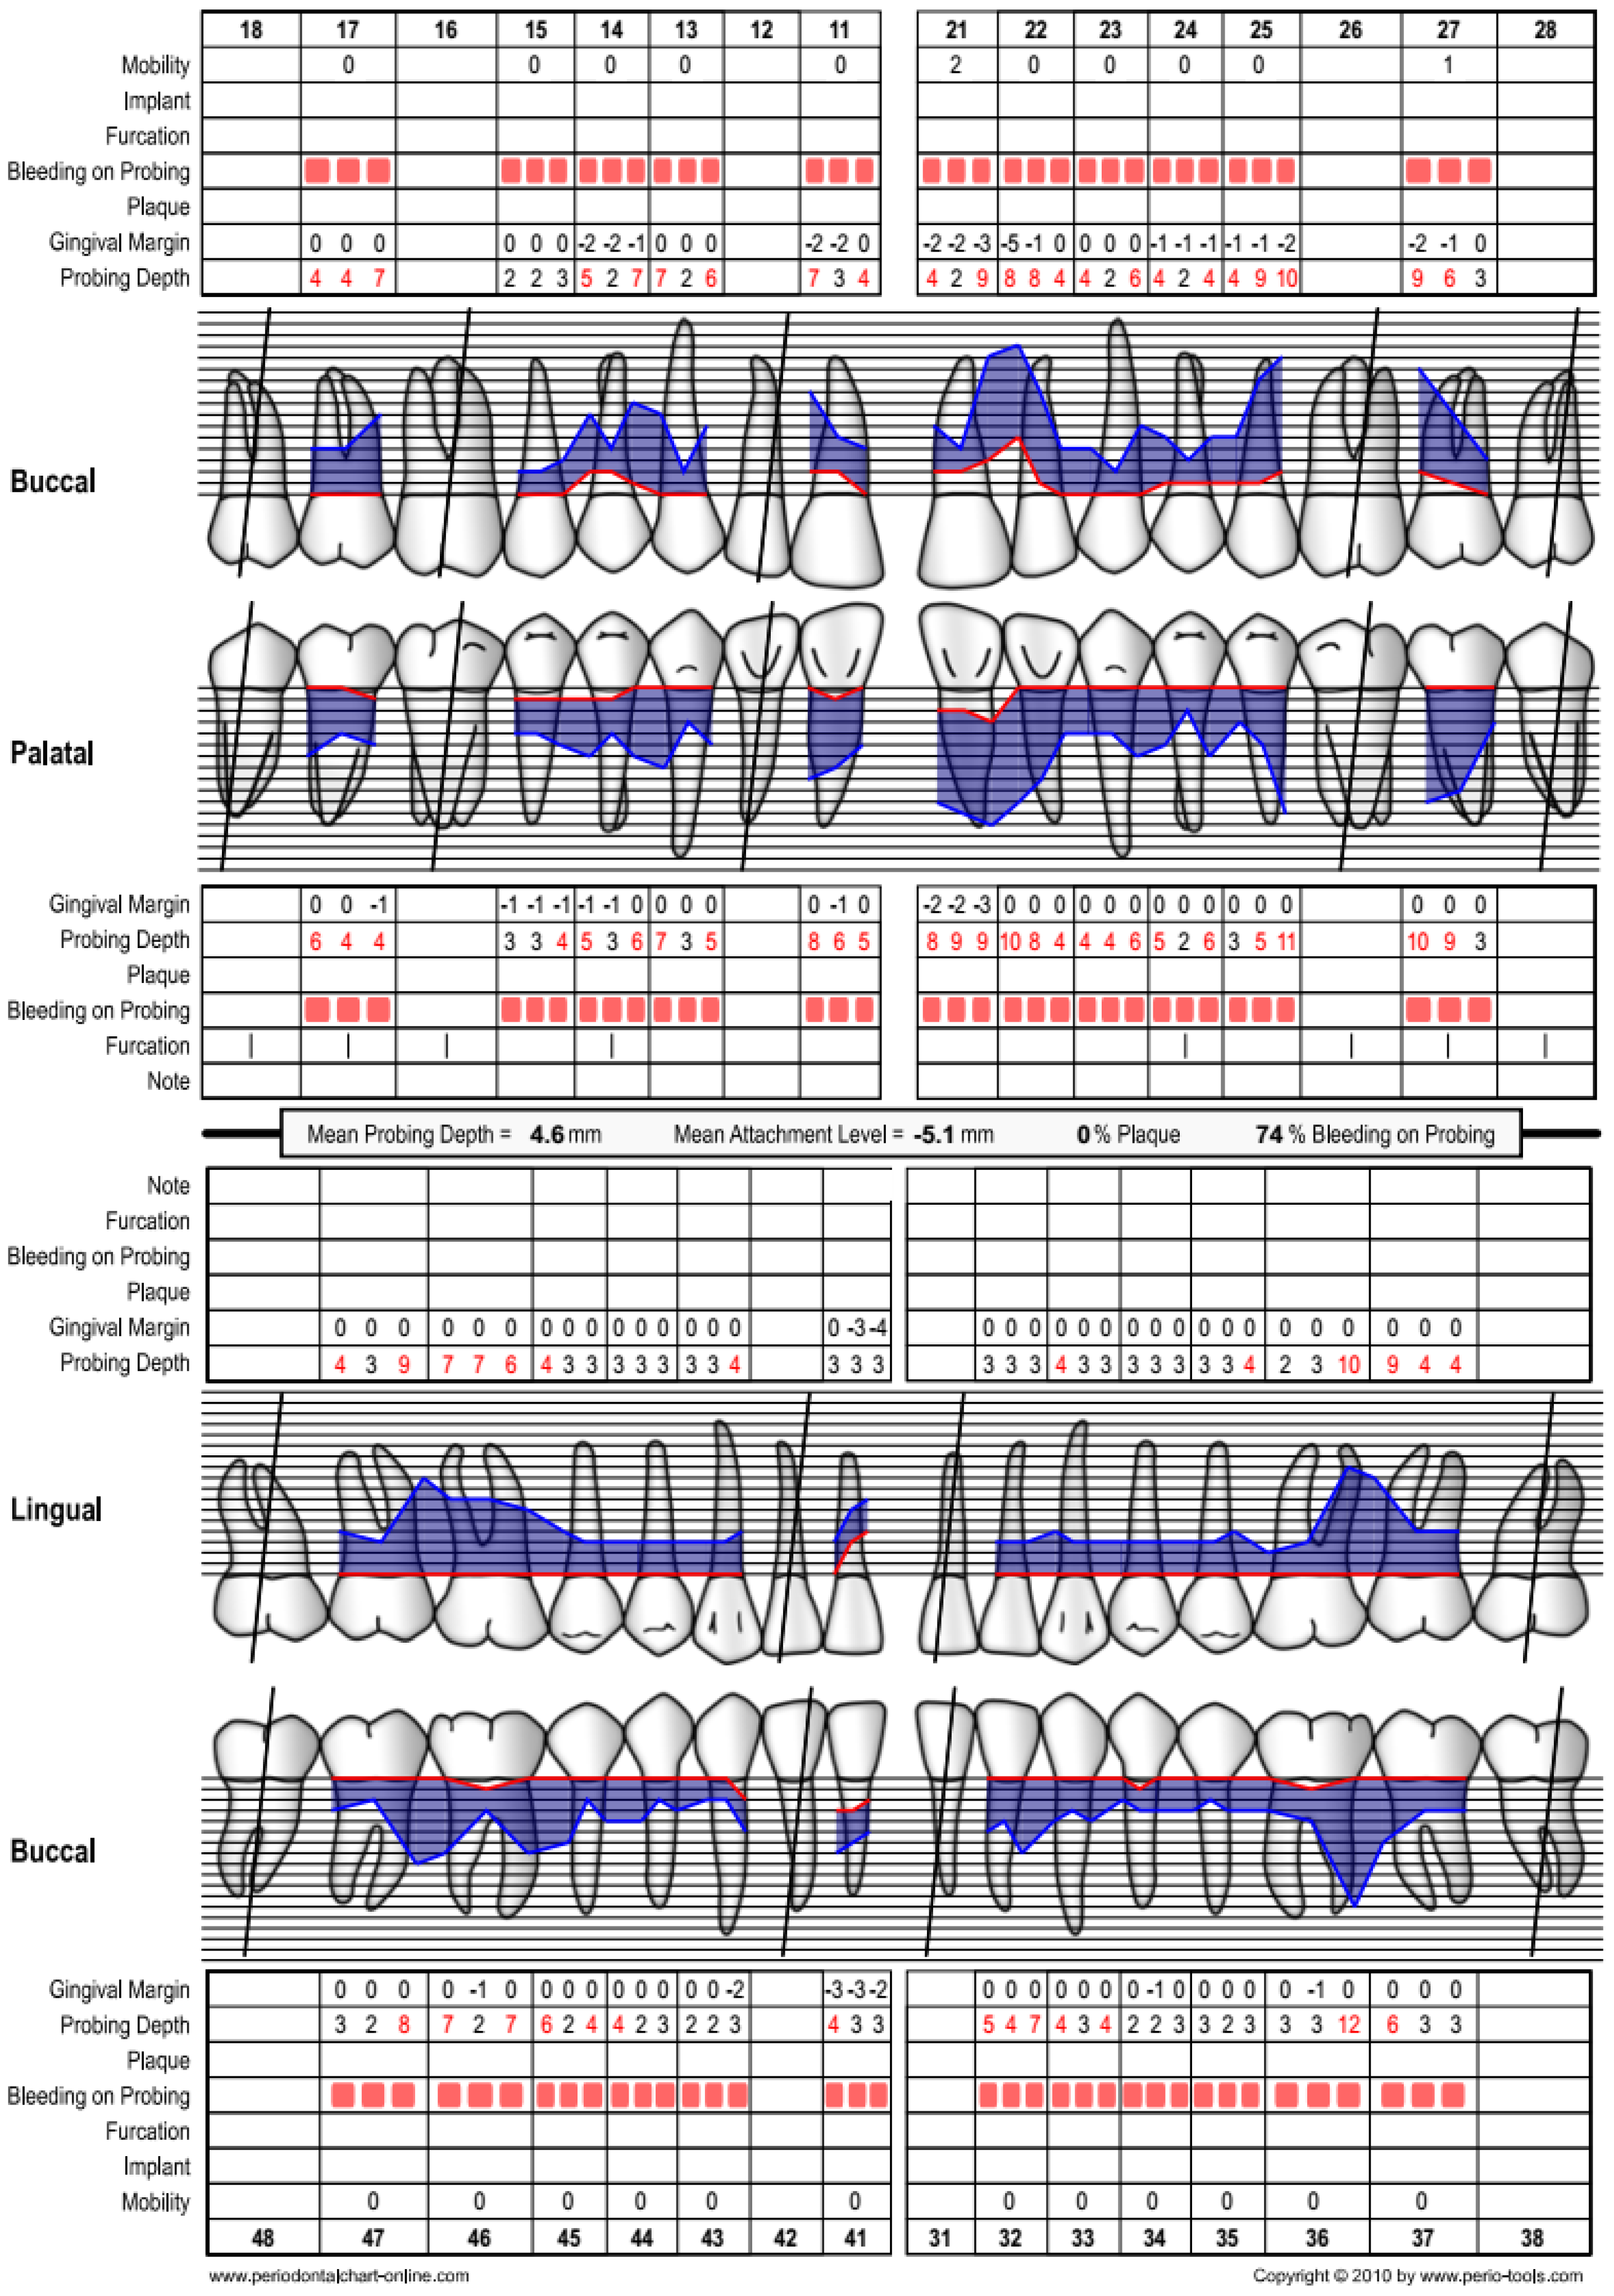

2.1. Case 1

2.2. Case 2

3. Results

| Baseline | 3 Months | 6 Months | 1 Year | 1.5 Years | 2 Years | 3 Years | 3.5 Years | 5 Years | |

|---|---|---|---|---|---|---|---|---|---|

| Vitality | + | + | + | + | + | + | + | + | + |

| PPD (mm) | 11 | N/A | 4 | 4 | 3 | 3 | 3 | 3 | 4 |

| PPD reduction compared to baseline (mm) | N/A | N/A | −7 | −7 | −8 | −8 | −8 | −8 | −7 |

| CAL (mm) | 13 | N/A | 6 | 6 | 5 | 5 | 5 | 5 | 6 |

| CAL gain compared to baseline | N/A | N/A | +7 | +7 | +8 | +8 | +8 | +8 | +7 |

| BOP | + | N/A | − | + | − | − | + | − | + |

| GR (mm) | 2 | N/A | 2 | 2 | 2 | 2 | 2 | 2 | 2 |

| % bone fill | N/A | N/A | N/A | 73 | N/A | 73 | NA | 73 | 71 |

| Baseline | 3 Months | 6 Months | 1 Year | 1.5 Years | 3 Years | |

|---|---|---|---|---|---|---|

| Vitality | + | + | + | + | + | + |

| PPD (mm) | 14 | N/A | 5 | 5 | 5 | 5 |

| PPD reduction compared to baseline (mm) | N/A | N/A | −9 | −9 | −9 | −9 |

| CAL (mm) | 16 | N/A | 8 | 8 | 8 | 8 |

| CAL gain compared to baseline | N/A | N/A | +8 | +8 | +8 | +8 |

| BOP | + | N/A | + | + | + | + |

| GR (mm) | 2 | N/A | 3 | 3 | 3 | 3 |

| % bone fill | N/A | N/A | 100 | 100 | 100 | 100 |